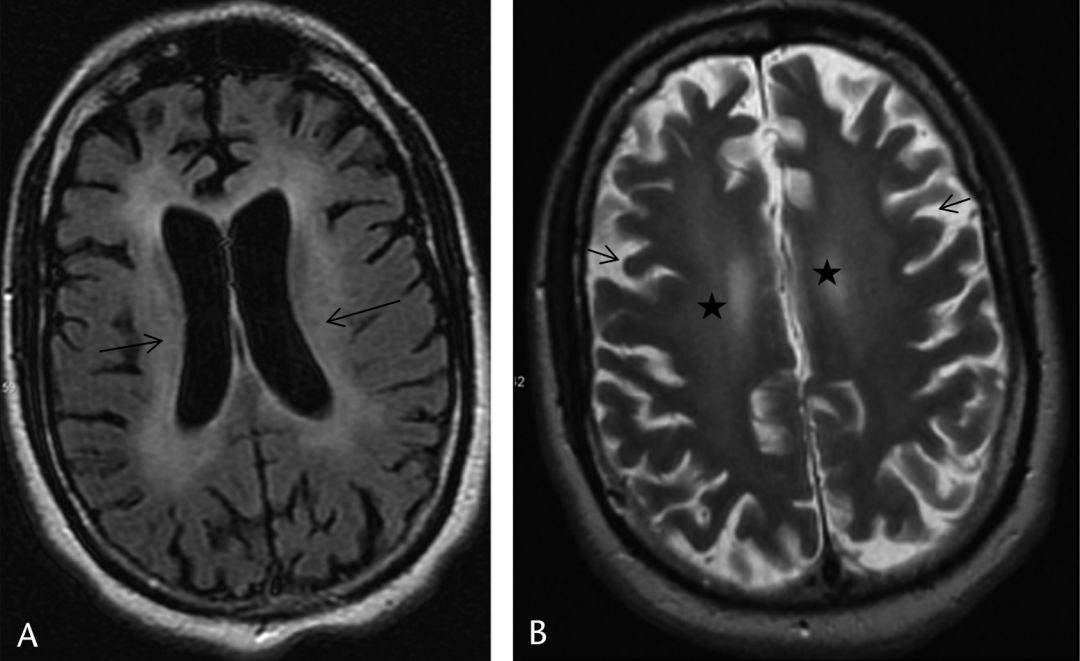

10月11日核磁如下:

3天后复查:

核磁只给了DWI序列,复查对比可见,双侧颞叶、岛叶、额叶皮层广泛、对称高信号,所谓皮层“花边征”。

1. 对称性双侧皮质受损,弥散受限、T2及FLAIR信号增高,特别是在岛叶和扣带回皮质,而在中央沟旁顶叶皮层、枕叶中央皮质及基底节区往往不受累。

2. 严重的损伤往往可影响上述相对不受累的区域,甚至基底节区、丘脑、皮质下白质及脑干也会受累。